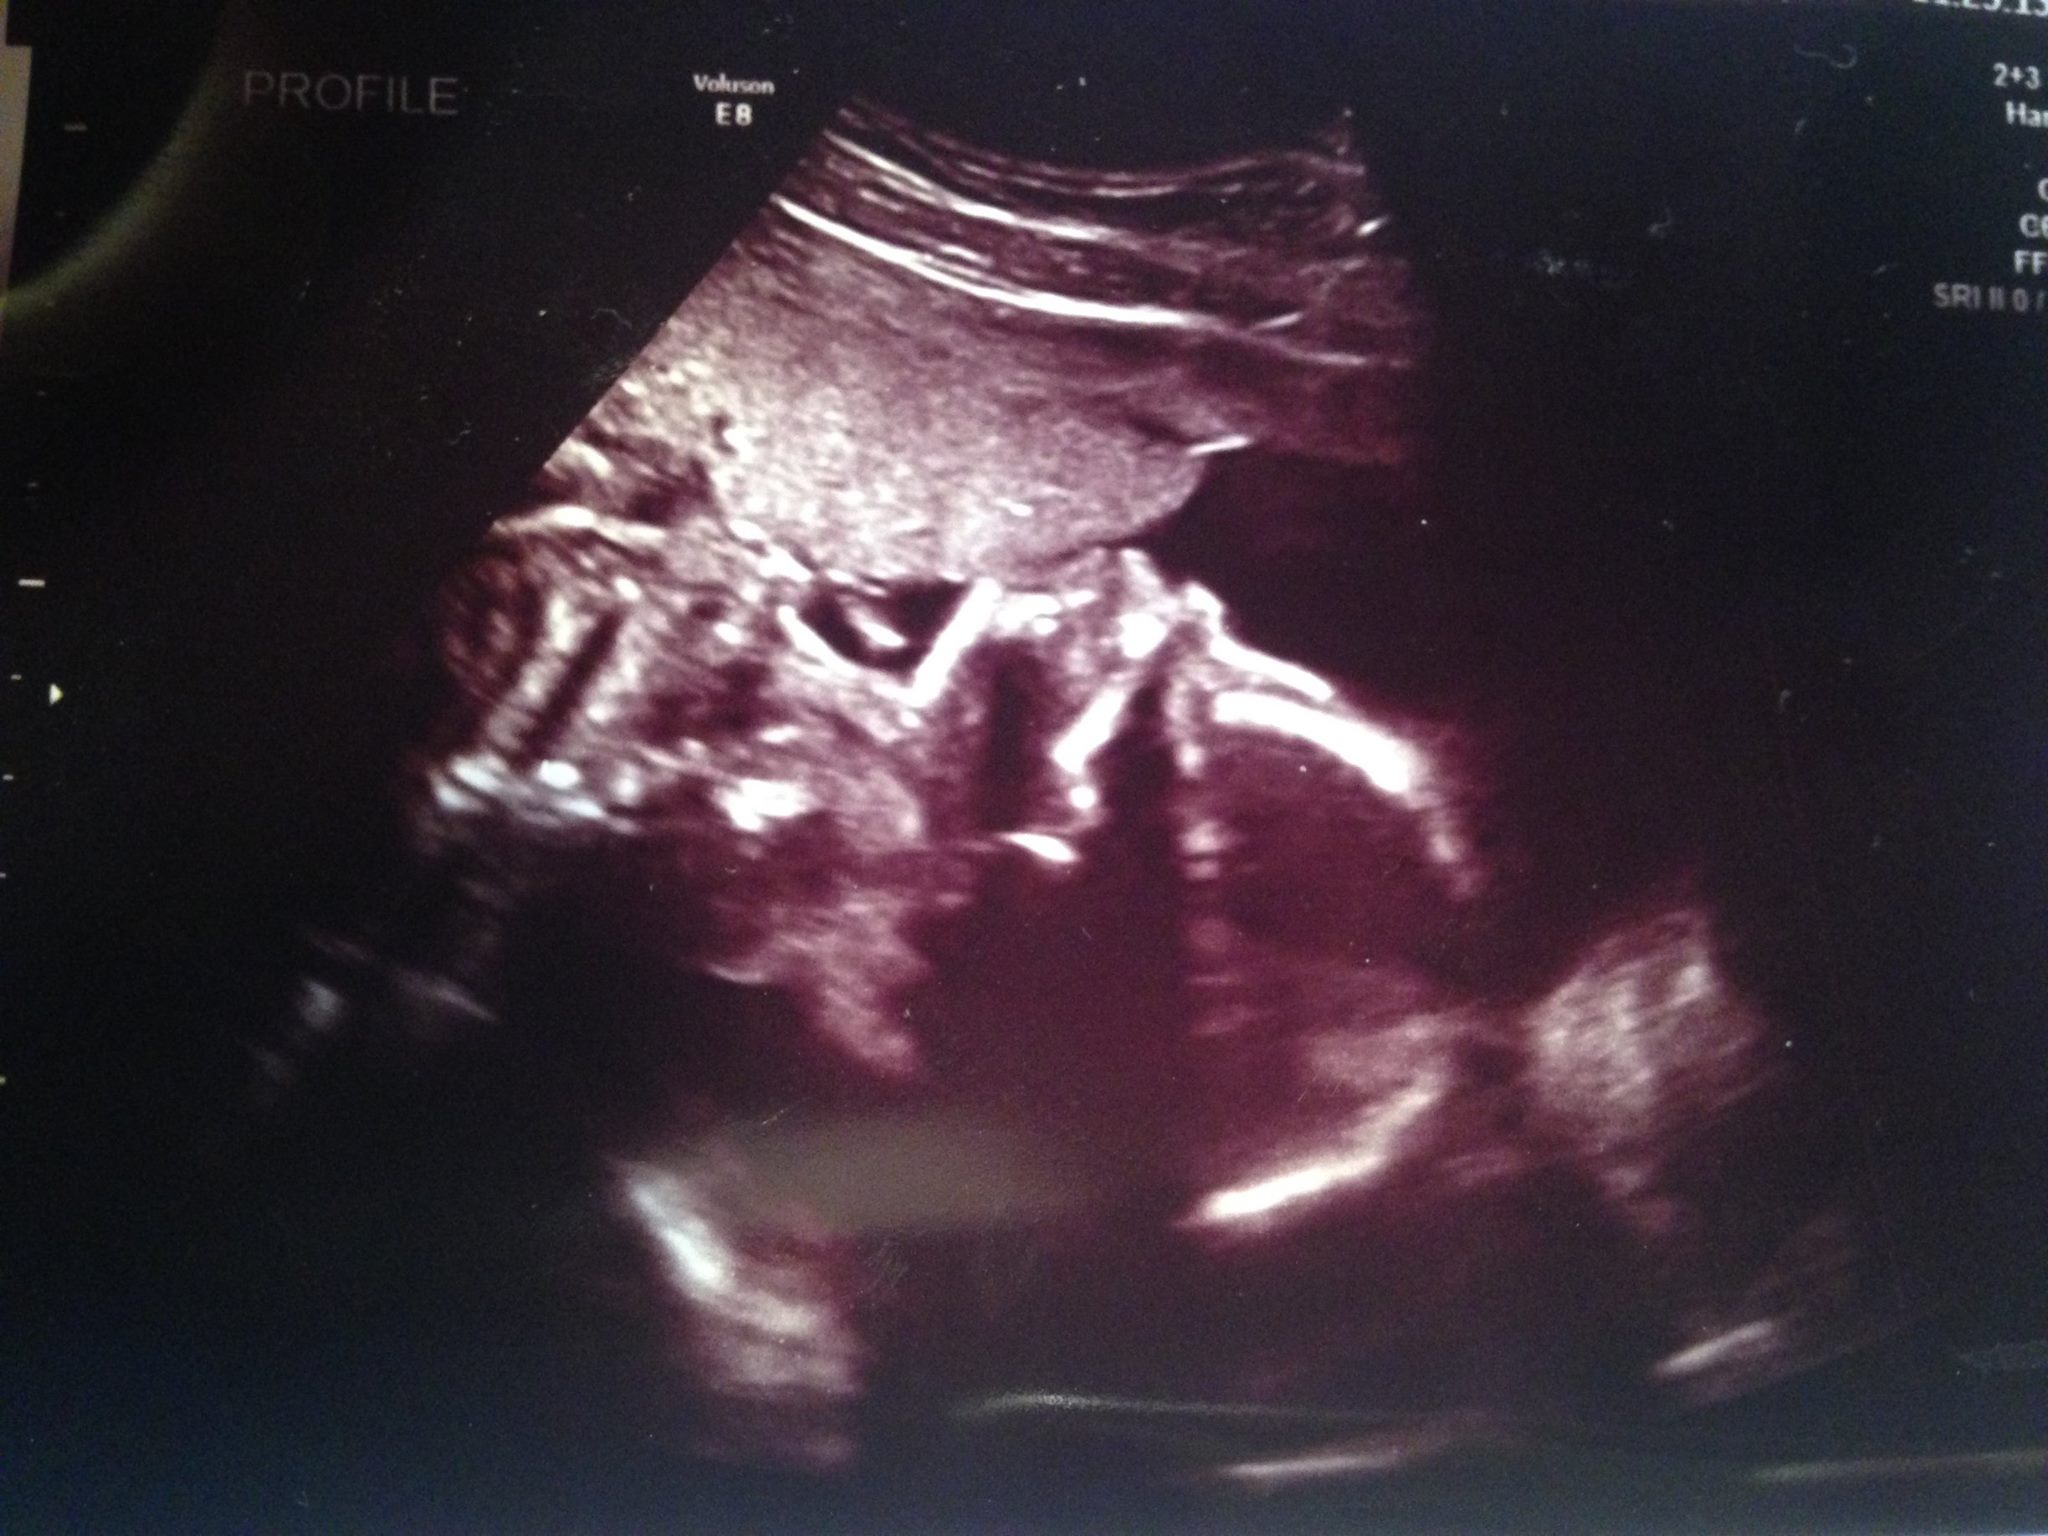

But it was during a routine checkup to find out the baby's gender that the young parents received some shocking news about their unborn baby boy.

It turned out that her unborn son had Down syndrome. She kept up a happy smile in public, but behind closed doors this young mom went through all the emotions; she was angry at all of the dreams that were shattered, hopeless for the future, she felt despair. Will her son be made fun of? Will her son be able to achieve independence?